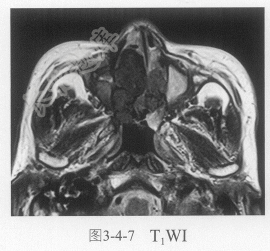

- 单项选择题4.进一步鼻窦MRI平扫及增强扫描见图3-4-7~图3-4-9。肿块信号特点是:

A、软组织肿块T

WI等稍高信号,T2WI为等低信号,增强扫描强化明显B、软组织肿块T

WI等信号,T2WI等信号,增强扫描无明显强化C、肿块多中心多发

D、鼻窦黏膜增厚,提示慢性炎症恶变

E、肿块没有什么特点